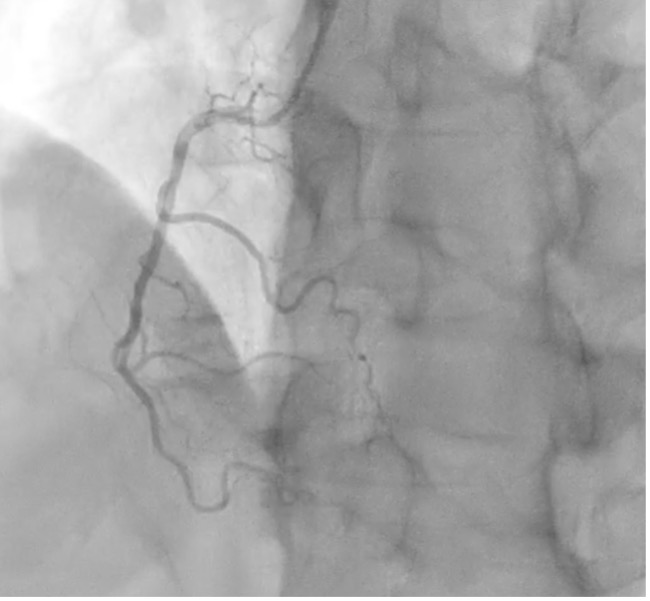

CAG shows mild diffuse stenosis at mid to distal LAD, severe diffuse stenosis at obtuse marginal, and mild diffuse stenosis at RCA (Pic 1, 2, 3).